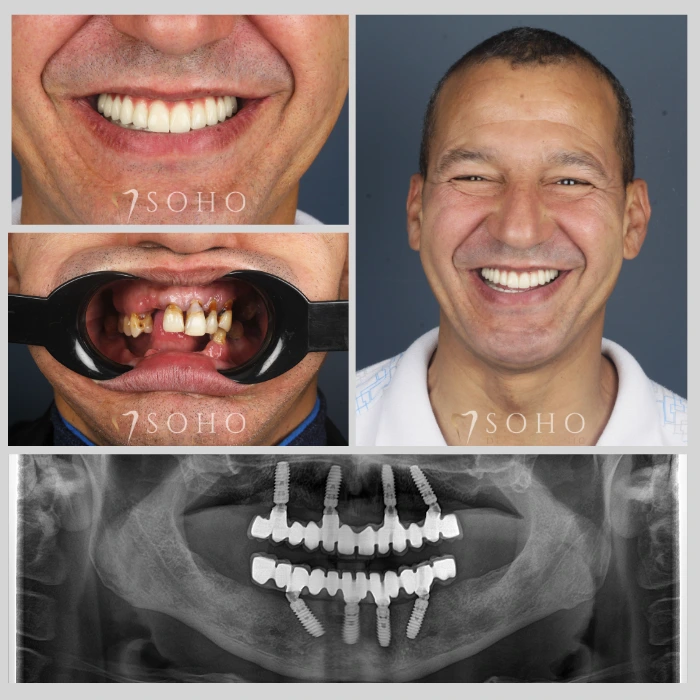

Real Patients. Real Smiles.

Explore the journey of our international patients through authentic visuals, elegant transformations, and moments captured inside Soho Dental Clinic. Let their stories inspire your own.

From First Visit to Final Smile.

Explore real patient stories captured in every transformation. These are more than smiles — they are renewed confidence, achieved with care and precision at Soho Dental Clinic.